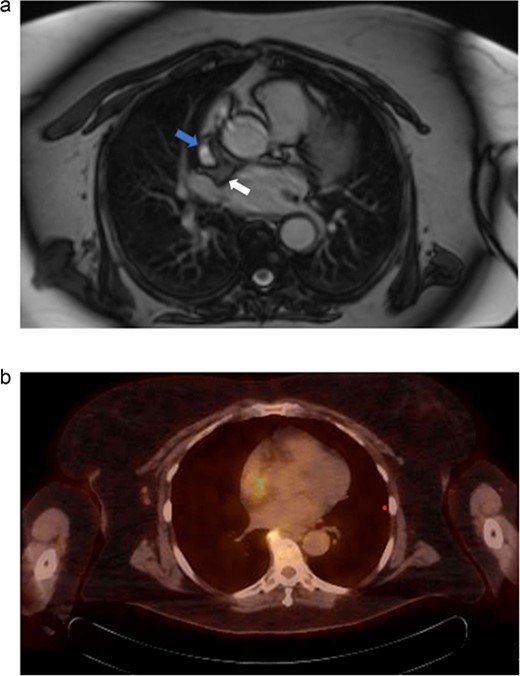

(a) Cardiac MRI. Mass is represented by the arrow on the right. The left arrow demonstrates the SVC. (b) PET/CT. Uptake is demonstrated in the right atrium. Uptake near the spine was determined to be artifact and not representative of metastatic disease.

Electrocardiography revealed normal sinus rhythm. An echocardiogram was performed, which revealed a mass involving the interatrial septum extending superiorly toward the superior vena cava (Fig. 1). She had normal biventricular function with a left ventricular ejection fraction of 55%, no valvular abnormalities, and no evidence of obstruction. Subsequently, cardiac magnetic resonance imaging (MRI) was performed. This showed a 5.5 cm x 2.5 cm x 2.5 cm mass involving the interatrial septum with near encasement of the superior vena cava (Fig. 1). The mass extended inferiorly toward the inferior vena cava (IVC) and coronary sinus, but without obvious involvement. The mass was hyperintense on T1 and T2-weighted sequences. On T1 fat saturating images, it was hypointense. It showed contrast enhancement with gadolinium suggesting vascularity. The staging workup further included positron emission tomography (PET), which showed increased fluorodeoxyglucose-18 (FDG) uptake in the atrial tumor without evidence of extracardiac disease or metastases (Fig. 2b). These findings were suggestive of a primary cardiac liposarcoma. The patient was then referred to our clinic for consideration of resection. She was deemed an operable candidate and the tumor resectable.